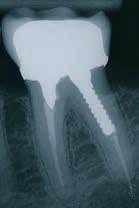

Under endelig udrensning af distale rodkanal i -6 skete fraktur af filstørrelse 40. Den frakturerede filspids efterlades, da den er umulig at fjerne. Ved efterfølgende rodspidsbetændelse pga. den efterladte fil kan det ende ud med ekstraktion af tand.

Filfraktur er desværre en – om end sjælden – ikke ukendt komplikation i forbindelse med rodbehandling. Filene er lavet af meget fleksible materialer, og de har generelt stor modstandsdygtighed overfor frakturer. Samtidig er filene meget gracile og udsættes for slid og forholdsvis kraftige belastninger. På trods af alle forholdsreglerne vil filfrakturer ikke

kunne undgås. Der bør dog alligevel være kontrol af de brugte file og deres anvendelse. Det foreslås, at der i klinikken er en procedure for håndtering af gamle file, som indeholder, hvornår filene skiftes, og hvordan de behandles under arbejdet. Fx ”alle file kasseres efter 3 x brug”, og ”der arbejdes kun med file i fugtige kanaler”.

Foto: Dansk Endodontiforening